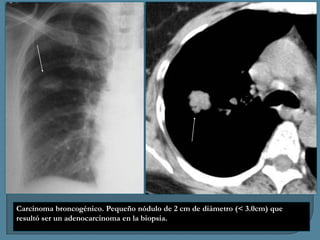

Carcinoma broncogénico. Pequeño nódulo de 2 cm de diámetro (< 3.0cm) que

resultó ser un adenocarcinoma en la biopsia.